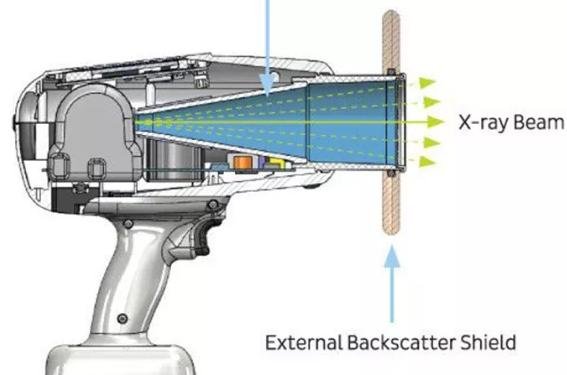

2. Radiation Safety

Radiation protection is a top priority. Choose a device that includes:

- FDA/CE/ISO certification

- Lead shielding or internal radiation protection

- Proper collimation to minimize scatter radiation

4. Weight and Ergonomics

Since dentists or technicians handle these devices directly, weight matters.

- Ideal weight: 2–3 kg for handheld units

- Ergonomic grip to reduce fatigue